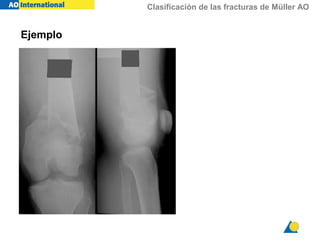

Ejemplo

Clasificación de las fracturas de Müller AO

¿Clasificación?

Hueso = 3

3

Segmento = 3

33

33-C

Tipo = C

33-C3

Grupo = 3

¿Hueso = ?

¿Hueso = 3 (fémur) ?

32

Hueso = 3 (fémur)

Segmento = 2 (diáfisis)

32-A

Tipo = A (simple)

32-A3

Tipo = A

Grupo = 3 (por flexión, <30º